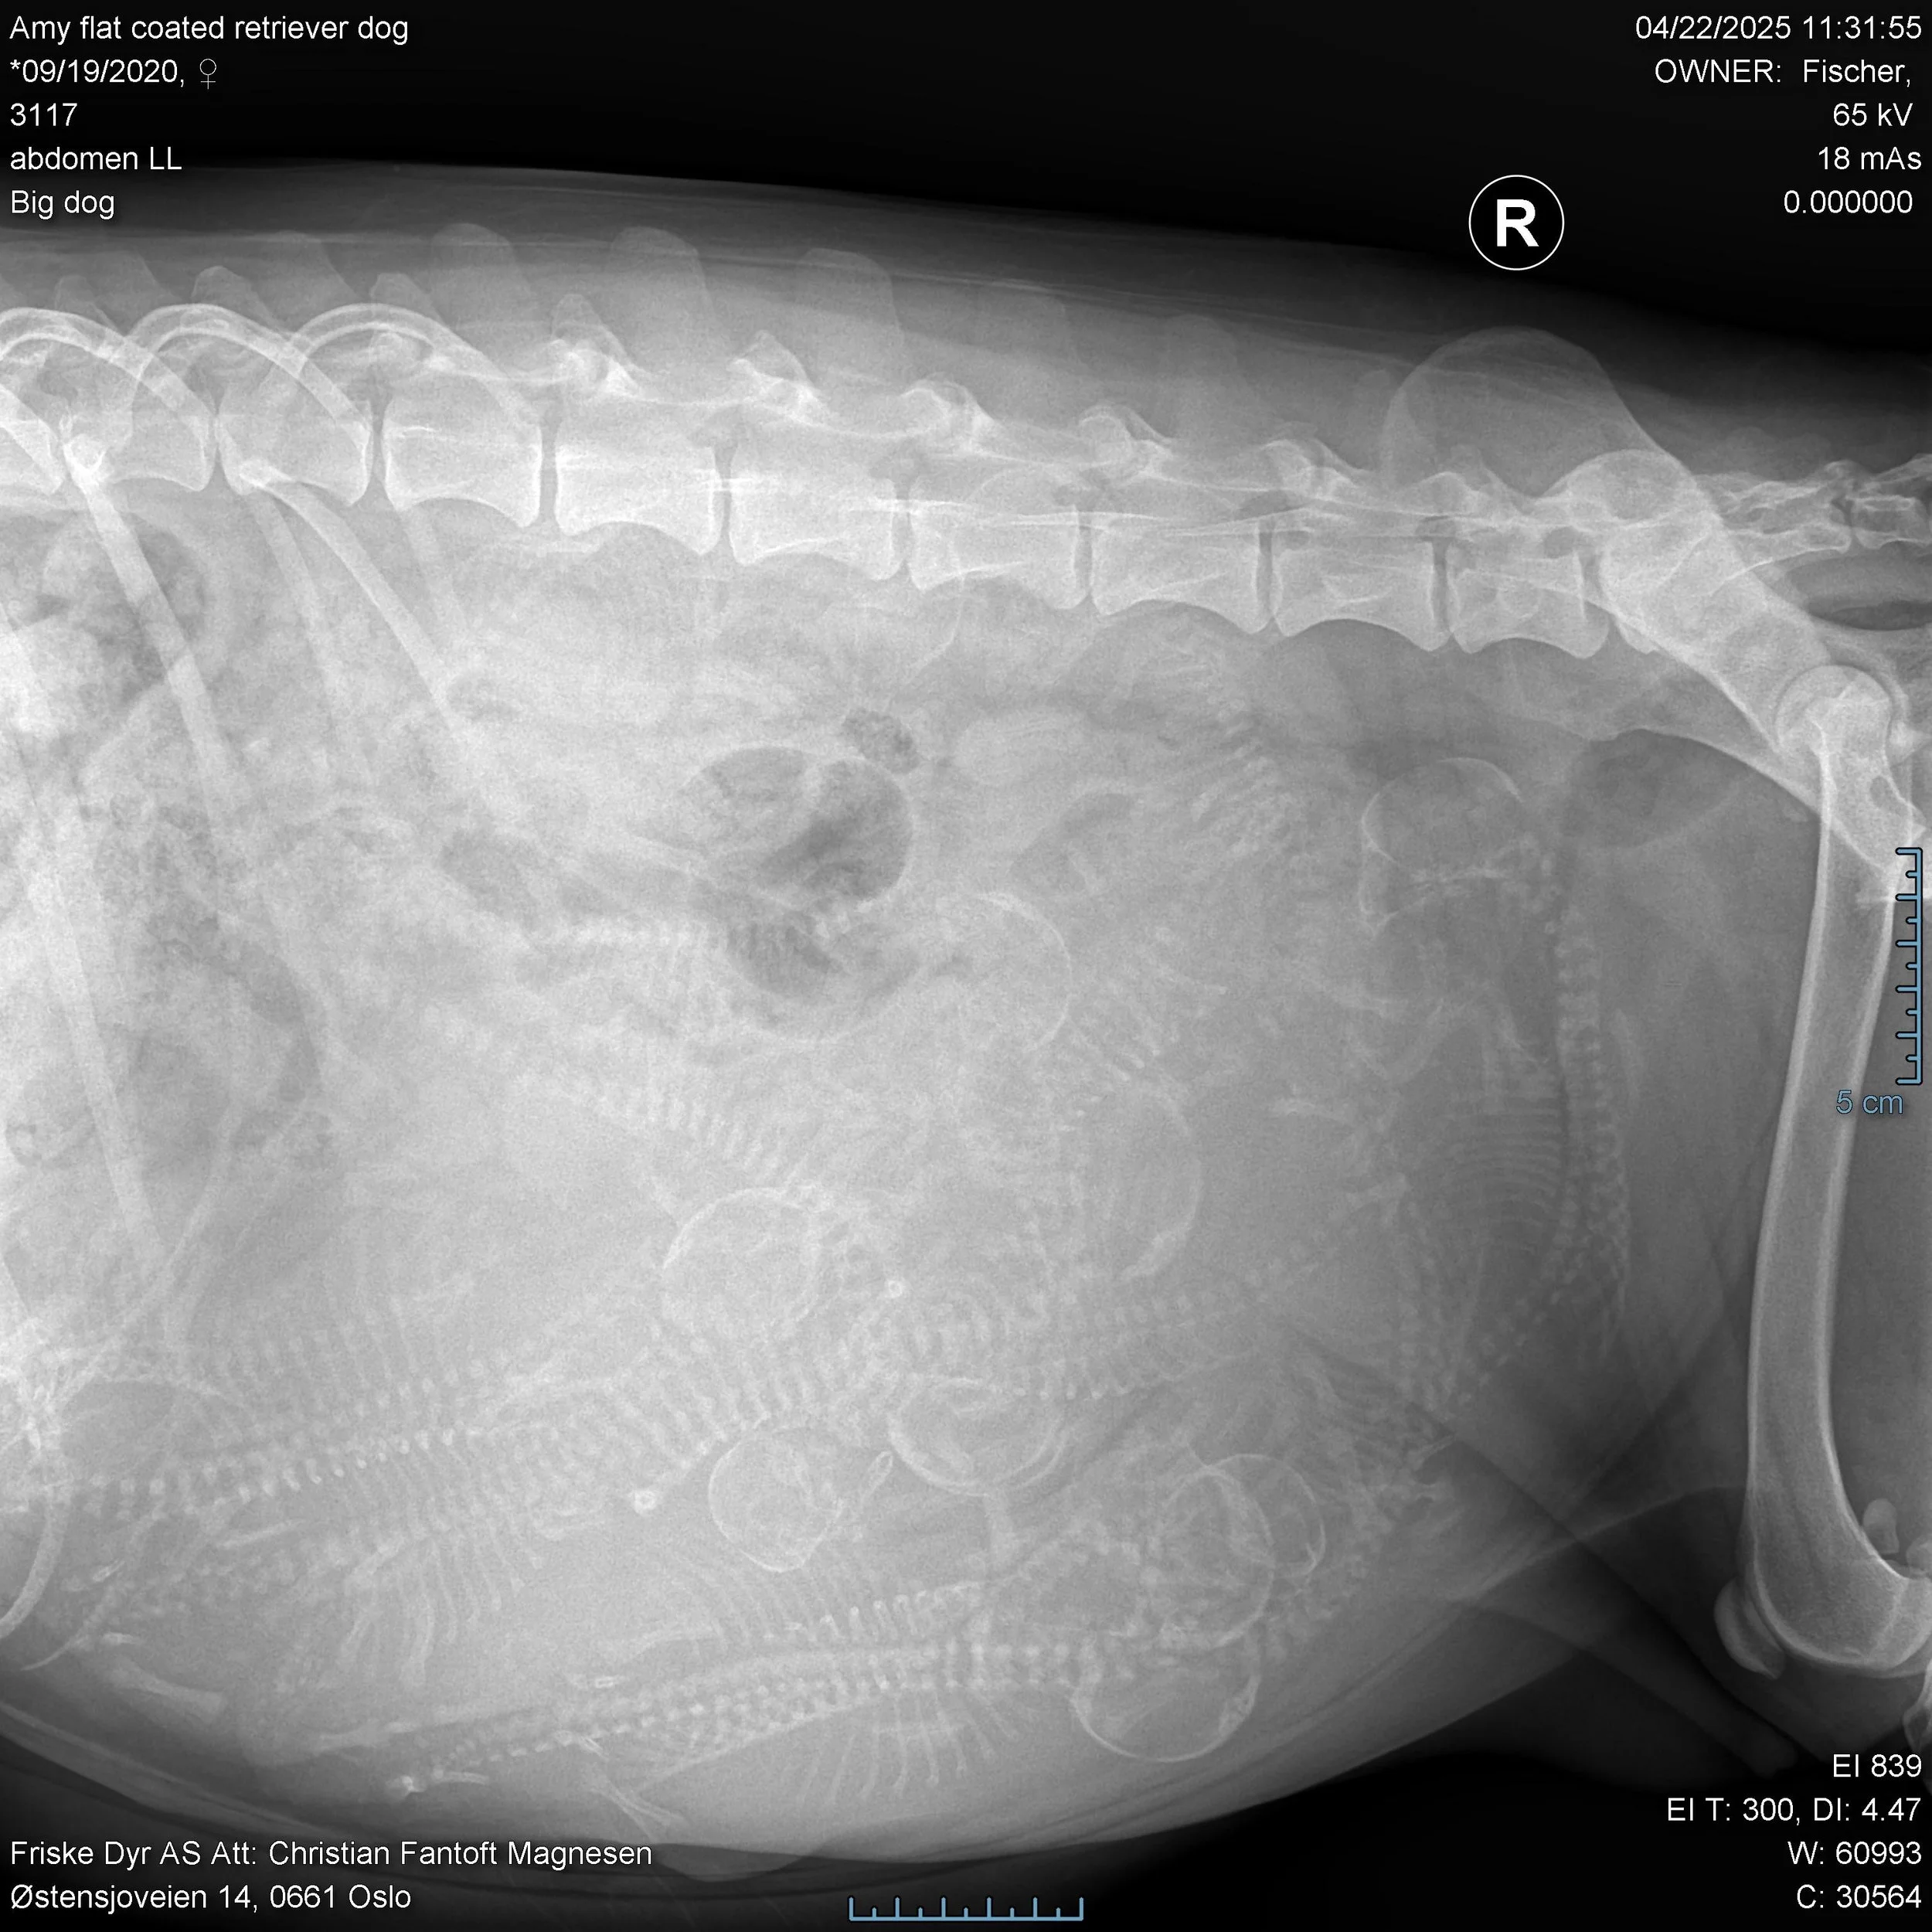

I dag har vi vært og tatt røntgenbilder av den store magen. Vi har jo trodd at det var ganske fullt der inne, men nå vet vi. Det vil si - det var vanskelig for veterinæren å telle -men han anslo at det var 12 til 13 valper.

Her er det bare å telle